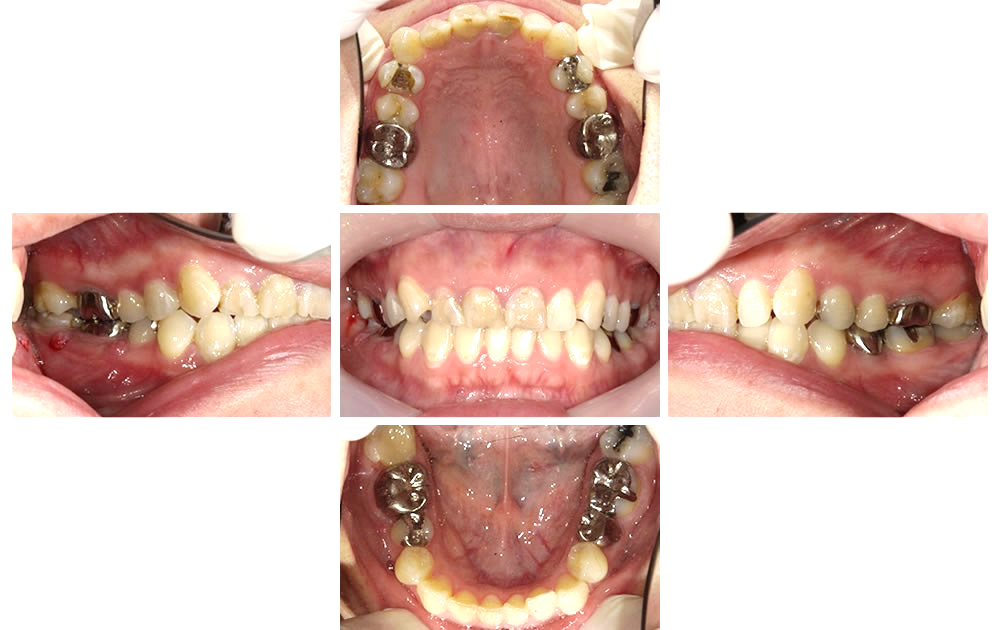

歯根が割れていた右下奥歯を抜歯後、親知らずを移植して咬み合わせを回復した症例をご紹介します。

【初診時口腔内写真】

こちらの患者さまは、右下奥歯が痛いとの主訴で来院されました。右下奥歯をピンセットで触ると、歯の動揺が確認できました。

(左)(中央)保存不可能な右下の奥歯を抜歯した状態です。

(右)上の親知らずの大きさを測り、移植する場所の大きさと検討します。

歯根膜と呼ばれる根の周囲の組織をなるべく傷つけないよう、上顎の親知らずを丁寧に抜歯しました。

その後、移植先にて歯の向きや角度を試行錯誤しながら収まりの良い位置を探します。

収まりの良い位置が決まったら、動かないように糸で縫い合わせて歯を固定します。

この状態で2週間ほど安定するのを待ちます。